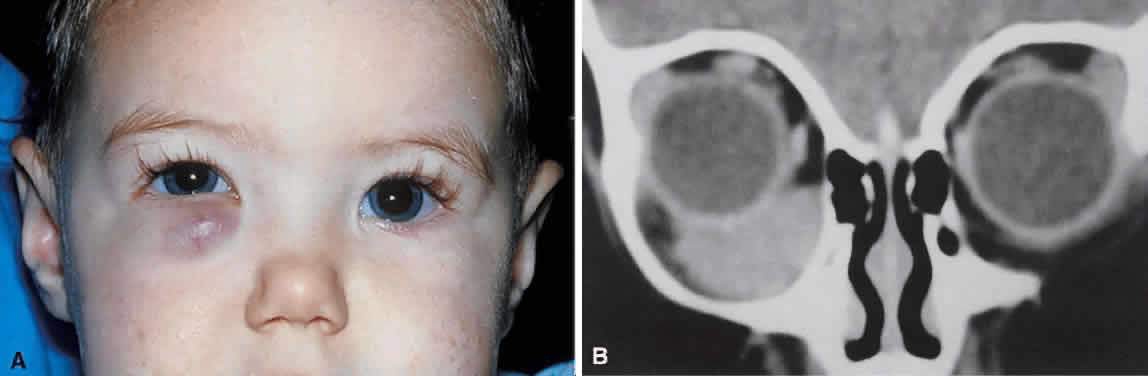

energy, the amplitude of the spikes falls off somewhat through the lesion (see Fig. 1B and C). MRI can help define the tumor's relationship to extraocular muscles (Fig. 2).  Fig. 1. A. Proptosis and downward, outward globe displacement developed over 2 days

in a 3-year-old girl. A homogeneous mass fills the superomedial orbit. B. Contact B-scanning shows a relatively well-circumscribed mass with uniform

internal echoes. C. Contact A-scanning shows the internal reflectivity to be of low to medium

amplitude, consistent with a sarcomatous lesion. Biopsy results confirmed

the diagnosis of rhabdomyosarcoma. Fig. 1. A. Proptosis and downward, outward globe displacement developed over 2 days

in a 3-year-old girl. A homogeneous mass fills the superomedial orbit. B. Contact B-scanning shows a relatively well-circumscribed mass with uniform

internal echoes. C. Contact A-scanning shows the internal reflectivity to be of low to medium

amplitude, consistent with a sarcomatous lesion. Biopsy results confirmed

the diagnosis of rhabdomyosarcoma.

Fig. 2. MRI shows an intraconal tumor of lower intensity than the medial rectus

muscle. The proximal muscle is splayed rather than compressed, suggesting

that the lesion originated within the medial rectus. The diagnosis

was alveolar rhabdomyosarcoma. Fig. 2. MRI shows an intraconal tumor of lower intensity than the medial rectus

muscle. The proximal muscle is splayed rather than compressed, suggesting

that the lesion originated within the medial rectus. The diagnosis

was alveolar rhabdomyosarcoma.